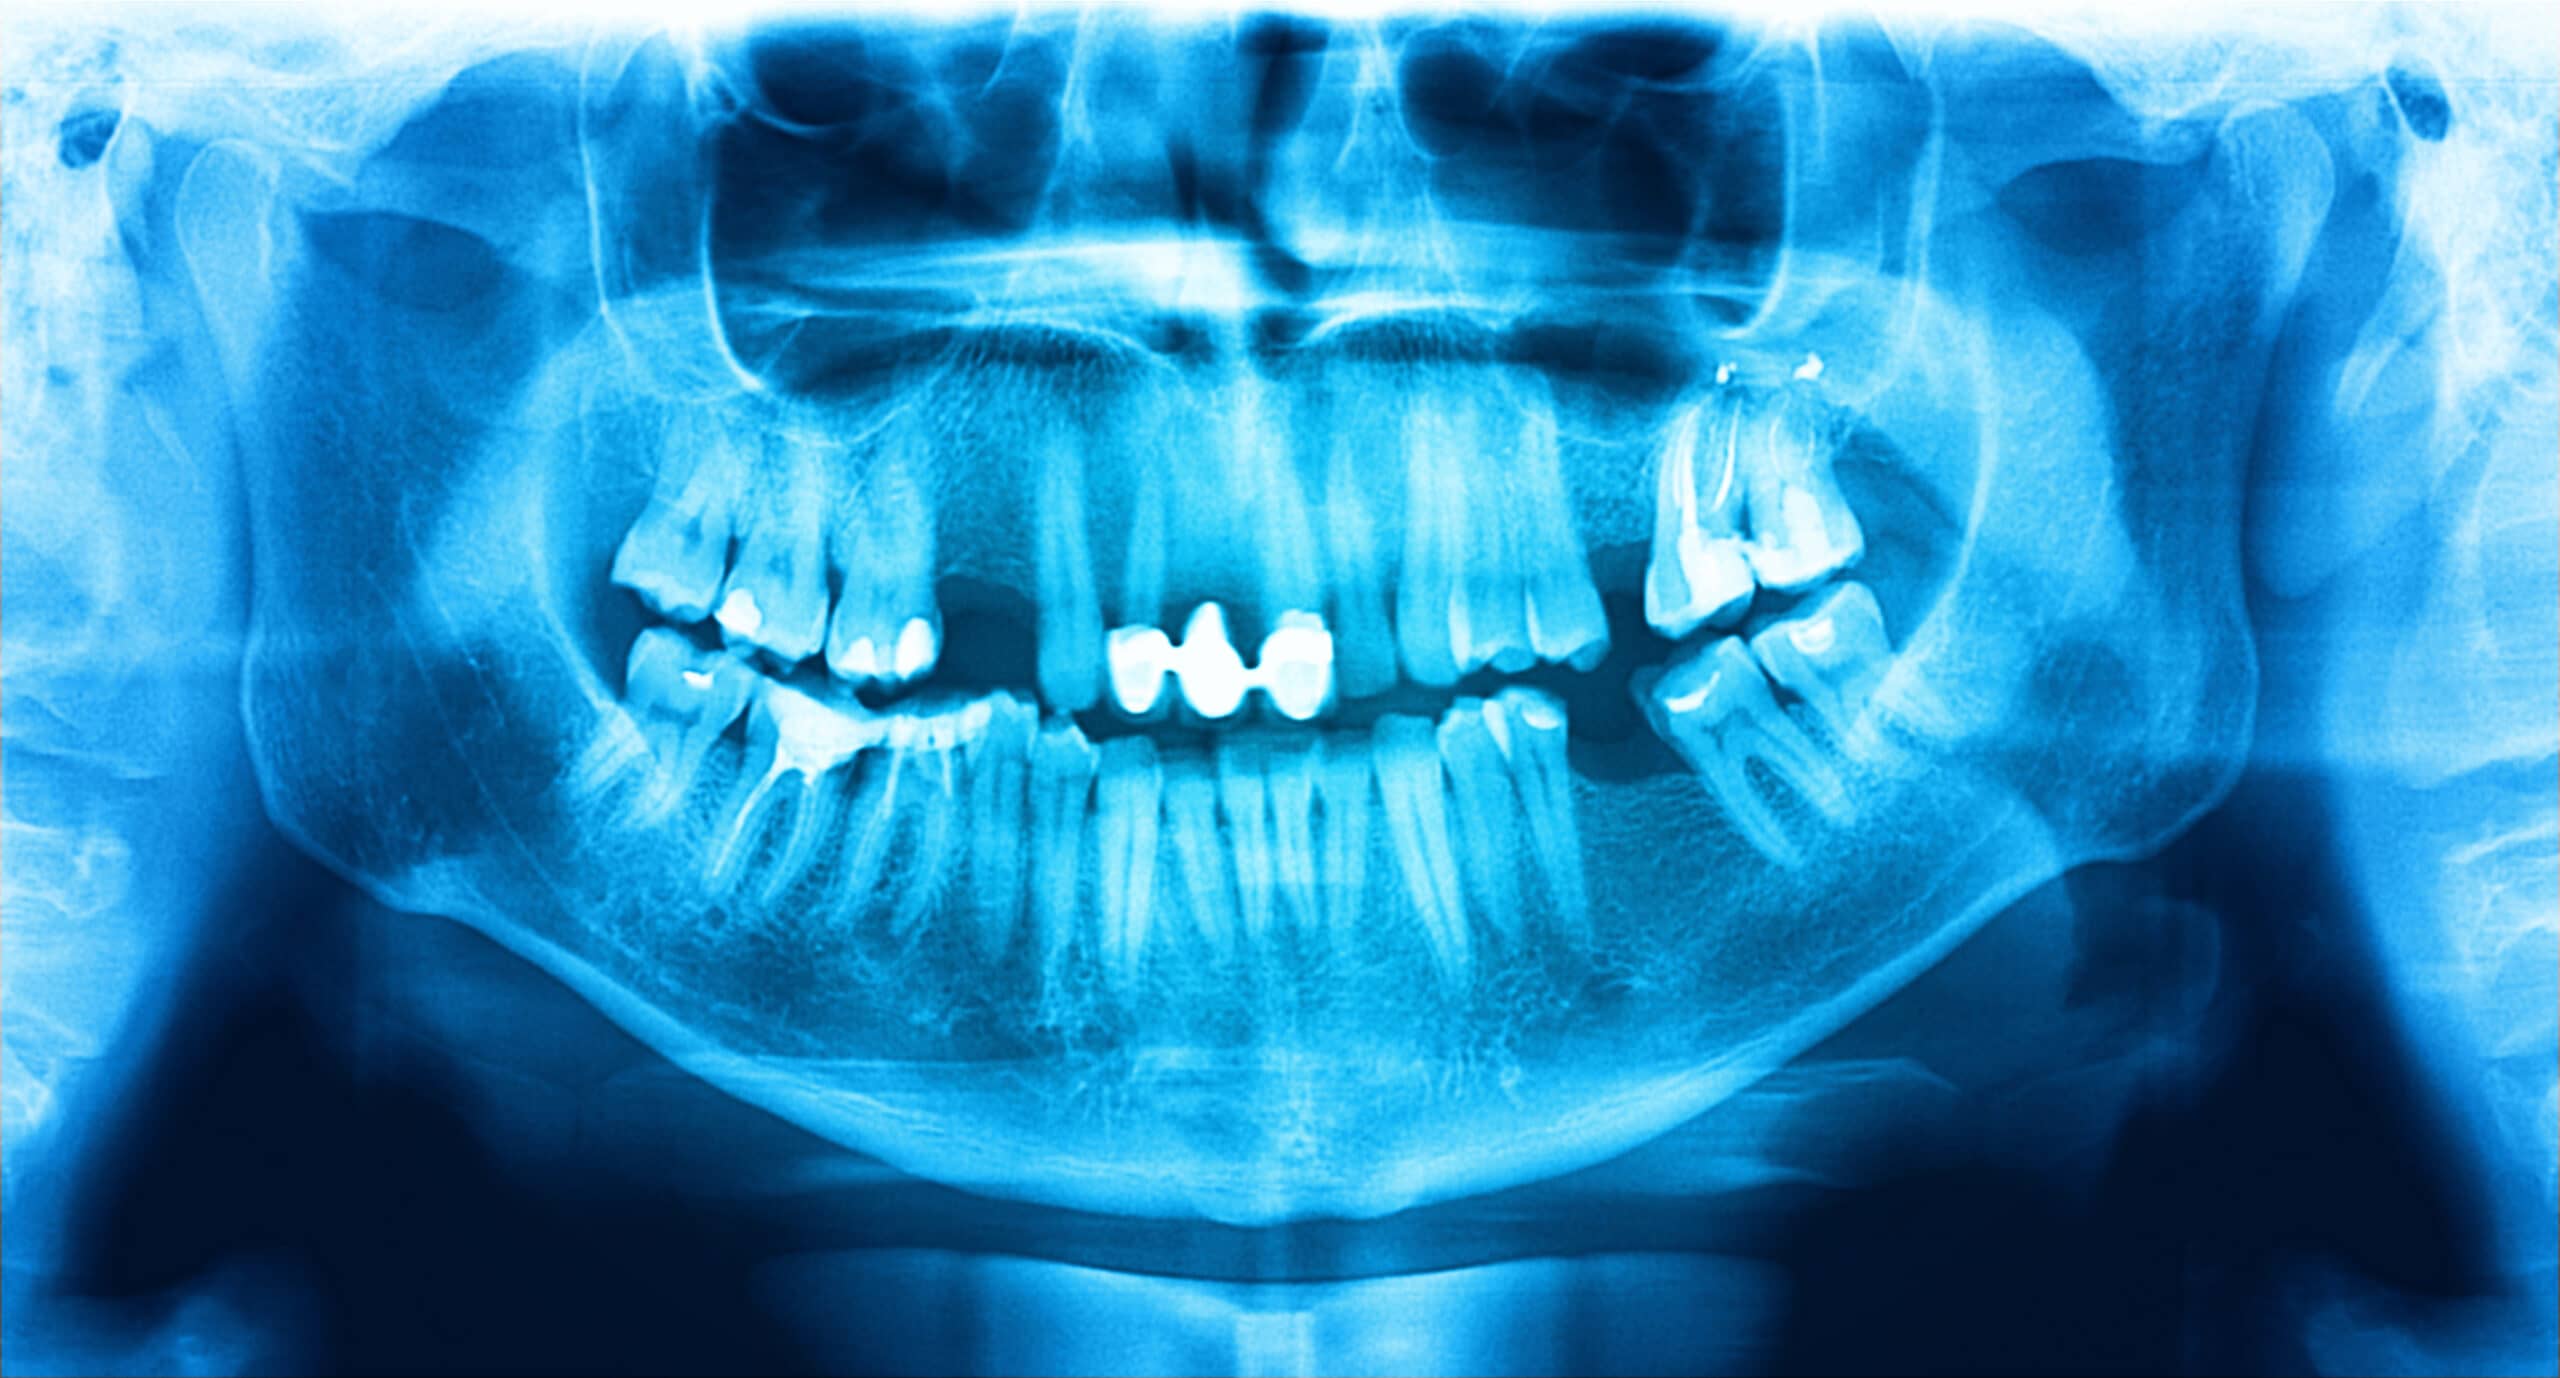

Premium Photo Digital dental panoramic radiograph taken with xray of Which Is Not A Use For Panoramic Radiographs In Dentistry Panoramic radiographs cannot be obtained in. Barriers do not need to be used, because spatter of blood and saliva is unlikely. Diagnosis of decay, periodontal disease, or periapical lesions Dental radiographs can broadly be divided in to two. Artefacts and errors can occur at any stage of obtaining a panoramic radiograph. Which is not a use for panoramic radiographs in. Which Is Not A Use For Panoramic Radiographs In Dentistry.